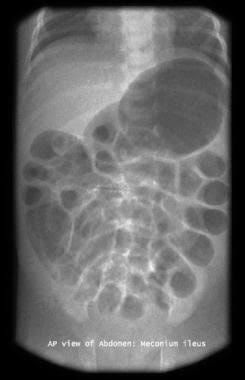

Meconium ileus results from the presence of impacted, abnormal thick meconium in the terminal ileum. It is a pathognomonic of cystic Fibrosis. It is present with bilious vomiting, abdominal distension, failure to pass meconium and mass in the right iliac fossa. Abdominal X-rays show: Dilated bowel loop without air fluid levels. "SOAP-BUBBLE" appearance in the right lower quadrant. Treatment is Gastrografin Enema for uncomplicated cases while surgical removal for complicated cases.